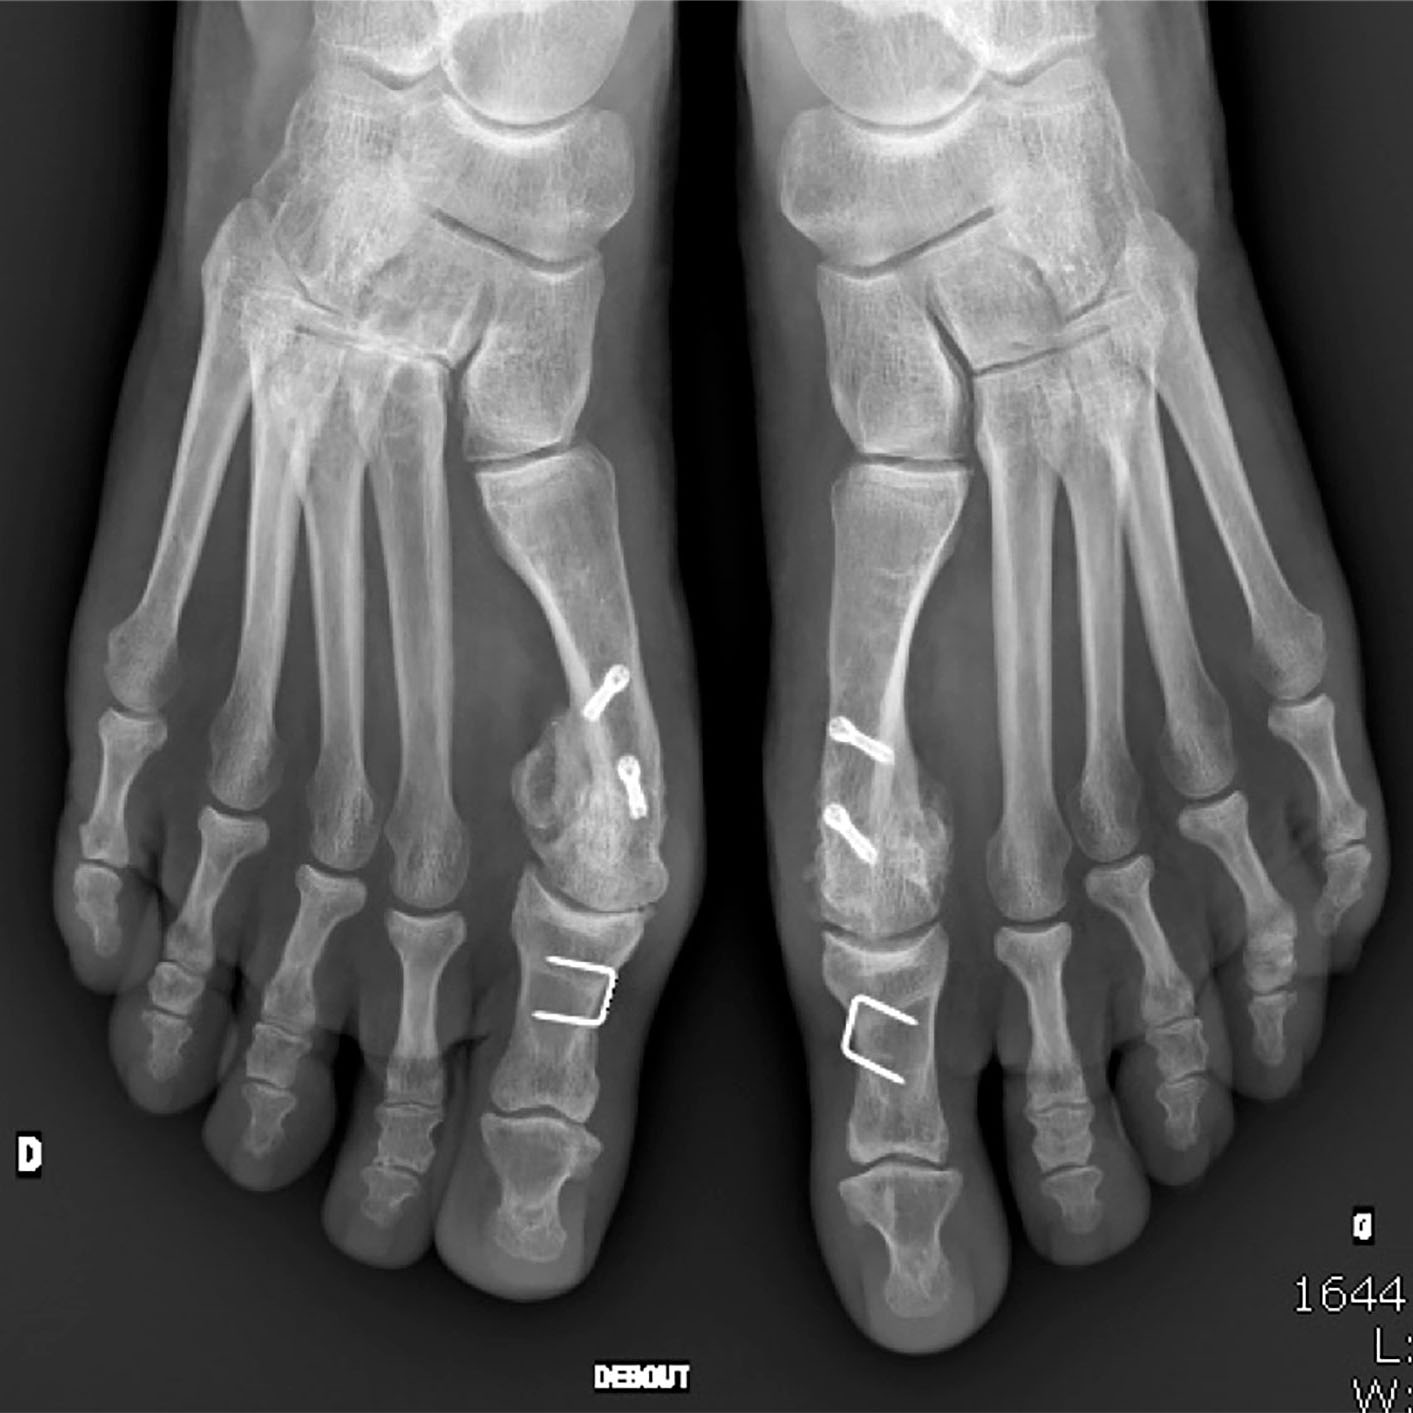

La radiographie est un examen d’imagerie médicale qui utilise les rayons X pour visualiser les structures internes de votre corps. Sa réalisation fait partie de notre cœur de métier et nécessite un savoir-faire technique et médical adapté à chaque pathologie suspectée. Différents clichés, appelés incidences,  pourront être réalisés en s’adaptant à la question posée par votre prescripteur et aux symptômes qui motivent votre venue dans notre centre.

• Certaines structures, en particulier les os ou le métal, arrêtent une partie de ces rayons.

• L’image est un négatif : les structures denses apparaissent blanches, les tissus mous apparaissent gris.

Radiographie images d'examen